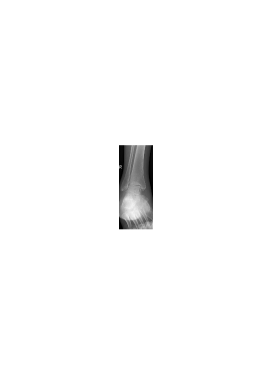

We illustrate now the suitability of the proposed mixed dictionary to produce high quality approximations of the set of X-ray medical images shown in Fig. 3. This set of twenty images is the Lukas 2D 8 bit medical image corpus, available on [33].

Image PSNR DWT DCT OMP2D HBW Hand1 48.1 30.0 26.4 39.0 72.6 Foot1 48.6 26.6 26.1 30.4 44.9 Foot0 48.6 25.5 26.1 42.7 65.2 Head0 47.4 25.3 24.3 51.9 63.2 Knee1 48.0 22.7 23.0 34.5 59.8 Sinus0 47.1 18.9 18.7 31.3 46.7 Hand0 48.8 18.6 18.7 32.2 47.9 Head1 46.4 17.5 15.1 38.3 44.4 Knee0 49.1 17.4 17.5 33.2 45.9 Sinus1 45.8 17.2 17.1 29.5 43.0 Breast0 44.3 15.7 15.3 36.7 41.0 Breast1 44.3 11.5 11.2 27.7 29.7 Thorax0 44.1 10.6 10.9 25.1 27.4 Thorax1 43.4 10.3 9.6 25.4 26.3 Leg0 48.9 8.2 8.4 21.2 22.3 Leg1 49.2 5.8 5.9 15.1 15.4 Pelvis1 44.3 4.8 4.7 12.3 12.6 Pelvis0 44.4 4.6 4.7 12.4 12.6 Spine1 47.0 3.5 3.6 9.3 9.4 Spine0 47.4 2.9 2.8 7.1 7.7